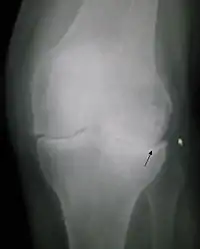

Radiografía

Para el estudio complementario de esta patología, encontramos diversos exámenes que pueden ser útiles, siendo el primero de todos, el uso de radiografía. Ésta resulta muy útil al momento de descartar otras patologías específicas y sobre todo en las condiciones a continuación descritas:[3]

Para reconocer una artrosis de rodilla gracias a una radiografía, se tiene que observar un espacio articular reducido y la presencia de osteofitos.[3]

De acuerdo a la escala de Kellgren y Lawrence se puede estudiar la progresión de la artrosis, estableciendo así distintos grados según diferentes criterios como lo son la presencia de osteofitos, los cambios en el hueso subcondral, entre otros.